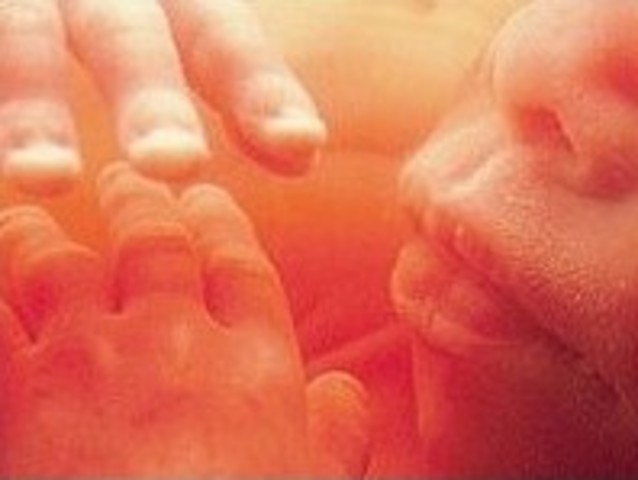

During this week the baby has grown to 13.5 inches and is now 1 and half pounds. The genitals are now fully developed and the sex of the baby can be figured out. Brain cells are maturing as the brain is growing rapidly. The hands are also fully developed.The blood vessels begin to develop and the nostrils are opening.

Fact: The inner bones of the ears have hardened so that the baby can hear more accurately

-The structures of the spine begin to form